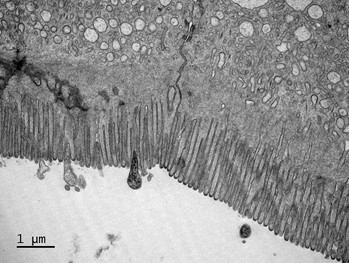

Parfois qualifié de « deuxième cerveau », notre tube digestif abrite un immense écosystème : le microbiote intestinal. Il regroupe l’ensemble des bactéries, levures et champignons qui vivent dans nos intestins.

Avec Karine Ricaud, découvrez comment ce microbiote joue un rôle clé dans la digestion, l’immunité, le métabolisme et même notre comportement. En s'appuyant sur les avancées récentes de la recherche, cette rencontre mettra en lumière les liens étroits entre intestin et cerveau.